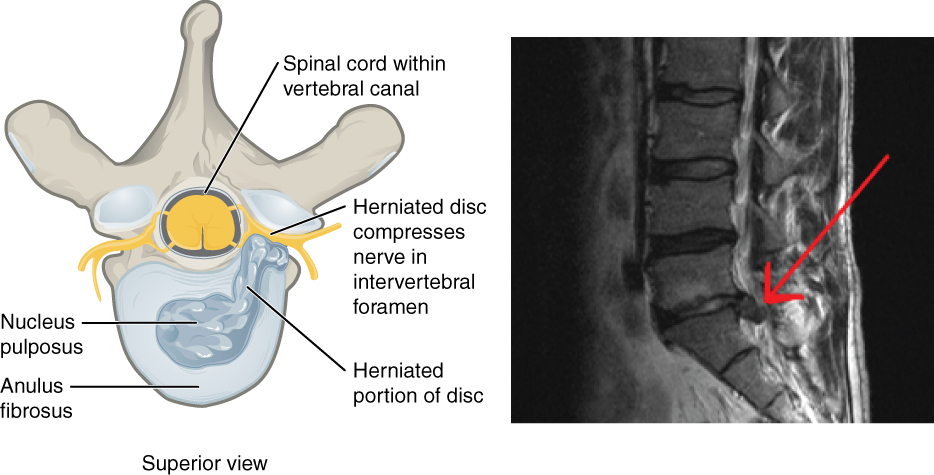

What is a Herniated Disc?

A herniated disc occurs when the inner gel-like material of a spinal disc, known as the nucleus pulposus, protrudes through a tear in the outer layer, called the annulus fibrosus. This condition usually happens in the lumbar or cervical region of the spine. Herniated discs can be caused by a variety of factors, including age-related degeneration, injury, or repetitive stress on the spine. According to the American Academy of Orthopaedic Surgeons, approximately 1-2% of the population experiences a herniated disc at some point in their lives. Notably, herniated discs are often asymptomatic, meaning many individuals may not realize they have one until they undergo imaging for other conditions. However, when symptoms arise, they can include severe pain, numbness, tingling, and weakness in the arms or legs. Understanding the anatomy of the spine and the mechanics behind disc herniation is crucial to grasp the severity and implications of this condition.